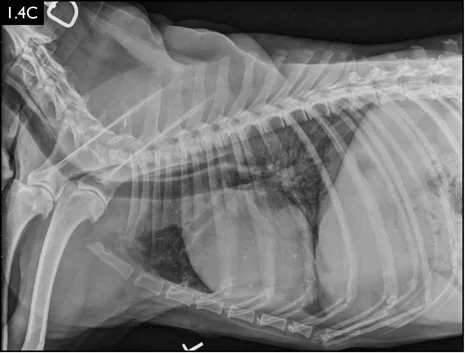

Diagnosis

Clinical signs can be strongly suggestive of bacterial pneumonia, but radiographs are important for confirmation, to characterize the disease (and potential etiology) and to provide a baseline for monitoring response to treatment (Figs. 1.4–1.6). A lag between clinical signs and radiographic changes can occur, and initial radiographs may be normal or appear discordant with clinical severity.

Fig. 1.4A–D Lateral and ventrodorsal radiographs of a dog with doxycycline-responsive pneumonia of unknown etiology before treatment ( A, B) and six days later ( C, D). Note the severe multilobar alveolar pattern that was present initially, most prominently in the left cranial lung lobe. (Courtesy of Atlantic Veterinary College)